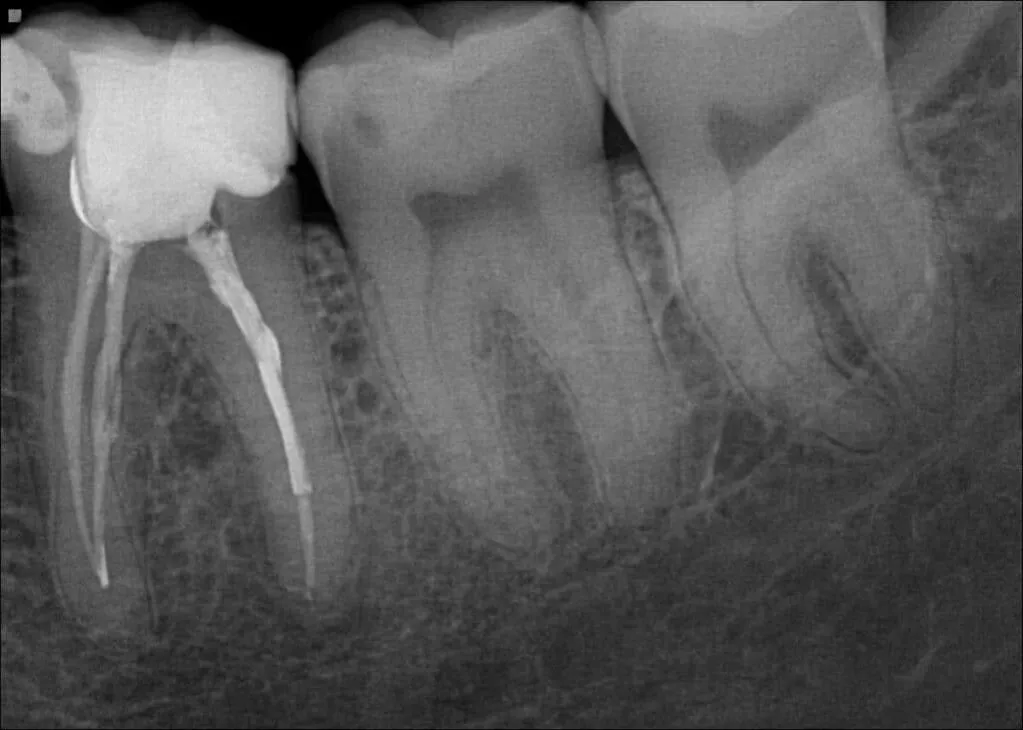

Kluczowym elementem diagnostyki bolącego zęba jest wykonanie zdjęcia rentgenowskiego (RTG). To prześwietlenie pozwala mi zajrzeć w głąb zęba i otaczających go struktur, których nie widać gołym okiem. Dzięki RTG mogę ocenić stan korzeni, sprawdzić, czy występuje stan zapalny w kości, określić głębokość ubytku próchnicowego oraz ogólną kondycję tkanek otaczających ząb. To bezcenne narzędzie, które często rozwiewa wszelkie wątpliwości diagnostyczne.

Leczenie kanałowe, czyli endodoncja, to procedura ratująca ząb przed usunięciem w przypadku nieodwracalnego zapalenia lub martwicy miazgi. Zabieg zawsze odbywa się w znieczuleniu miejscowym, dzięki czemu jest komfortowy dla pacjenta. Polega on na usunięciu zainfekowanej lub martwej miazgi z wnętrza zęba. Następnie dokładnie oczyszczam i dezynfekuję kanały korzeniowe, usuwając wszystkie bakterie. Ostatnim etapem jest ich szczelne wypełnienie specjalnym materiałem, co zapobiega ponownej infekcji i zabezpiecza ząb na długie lata.